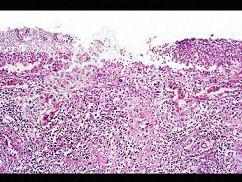

- 多项选择题根据图,关于菌痢的病理改变对的是 ( )

A、整个肠粘膜有假膜覆盖,粘膜上皮及腺体大片消失

B、假膜主要为纤维素、坏死的肠粘膜、细菌、嗜中性粒细胞及红细胞等,部分有脱落

C、粘膜下层、肌层、浆膜层有明显的炎症反应

D、大约一周左右,假膜开始脱落,形成大小不等,形状不一的“地图状”溃疡图

E、黏膜充血、水肿、中性粒细胞和巨噬细胞浸润